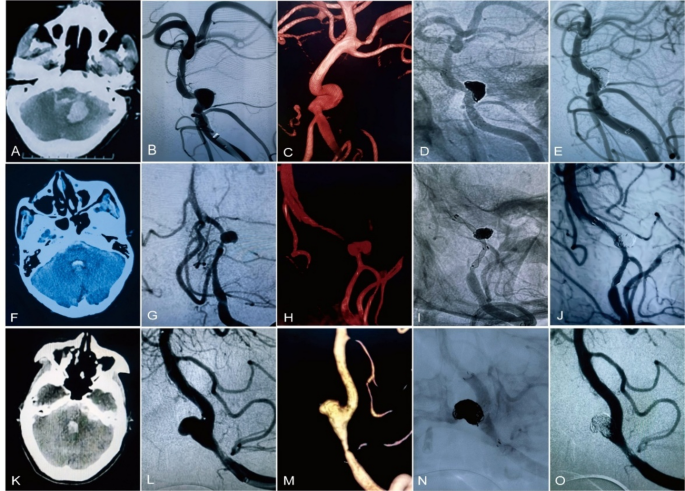

Case 1

A 64-year-old female patient exhibited a ruptured dissecting aneurysm in the basilar artery, accompanied by severe headaches, nausea, and vomiting. (Fig. 1B, C). Upon admission, her condition was assessed as Hunt-Hess grade II, with a modified Fisher score of 3, a NIHSS score of 7 and a mRS score of 3 (Fig. 1A). Following comprehensive preoperative preparation, the ruptured dissecting aneurysm was successfully treated using the double stent overlap technique. Initially, an enterprise 2 stent (4 × 23 mm) was deployed, followed by a LEO stent (3.5 × 25 mm), in conjunction with coil embolization to effectively occlude the false lumen and reconstruct the parent artery (Fig. 1D). The patient did not develop any new neurological deficits post-operation and was discharged seven days later. Nine months following the endovascular treatment, angiographic imaging confirmed the absence of aneurysm recurrence (Fig. 1E).

Case 2

A 57-year-old female manifesting acute severe headache secondary to a ruptured left V4 segment vertebral artery dissecting aneurysm underwent comprehensive preoperative evaluation, revealing Hunt-Hess grade II, modified Fisher grade III, NIHSS 6, and mRS 3 (Fig. 1F-H). The lesion was effectively treatment via overlapping dual-stent deployment strategy with an enterprise 2 stent (4 × 16 mm) and a LEO baby stent (2.5 × 25 mm) (Fig. 1I). Six-month post-endovascular intervention, angiographic surveillance demonstrated Raymond-Roy Occlusion Classification Grade I aneurysm occlusion (Fig. 1J).

Case 3

A 74-year-old patient with a ruptured left vertebrobasilar artery dissecting aneurysm (VBDA) underwent preoperative evaluation, revealing Hunt-Hess grade II, revised Fisher grade III, NIHSS score of 6, and mRS score of 3 (Fig. 1K-M). The dissecting aneurysm was successfully embolized using an overlapping dual-stent deployment strategy combining an enterprise 2 stent (4 × 23 mm) and a LEO stent (3.5 × 25 mm) (Fig. 1N). Six-month angiographic follow-up confirmed successful occlusion without evidence of recurrence (Fig. 1O).

Exemplar cases of ruptured vertebrobasilar dissecting aneurysms (VBDA) managed via overlapping dual-stent strategies. (A–D) A ruptured basilar artery (BA) dissection underwent endovascular coiling with adjunctive Enterprise 2 and LEO stent deployment. Nine-month follow-up angiography (E) confirmed complete aneurysm obliteration. (F–I) A left V4 vertebral artery (VA) ruptured dissection was treated with coiling supported by Enterprise 2 and LEO Baby stents. Six-month surveillance (J) demonstrated stable occlusion (Raymond-Roy Occlusion Classification [RROC] Grade I). (K–N) A vertebrobasilar dissection received coiling augmented by an Enterprise 2-LEO stent construct. Six-month imaging (O) revealed parent vessel patency with successful aneurysm exclusion.